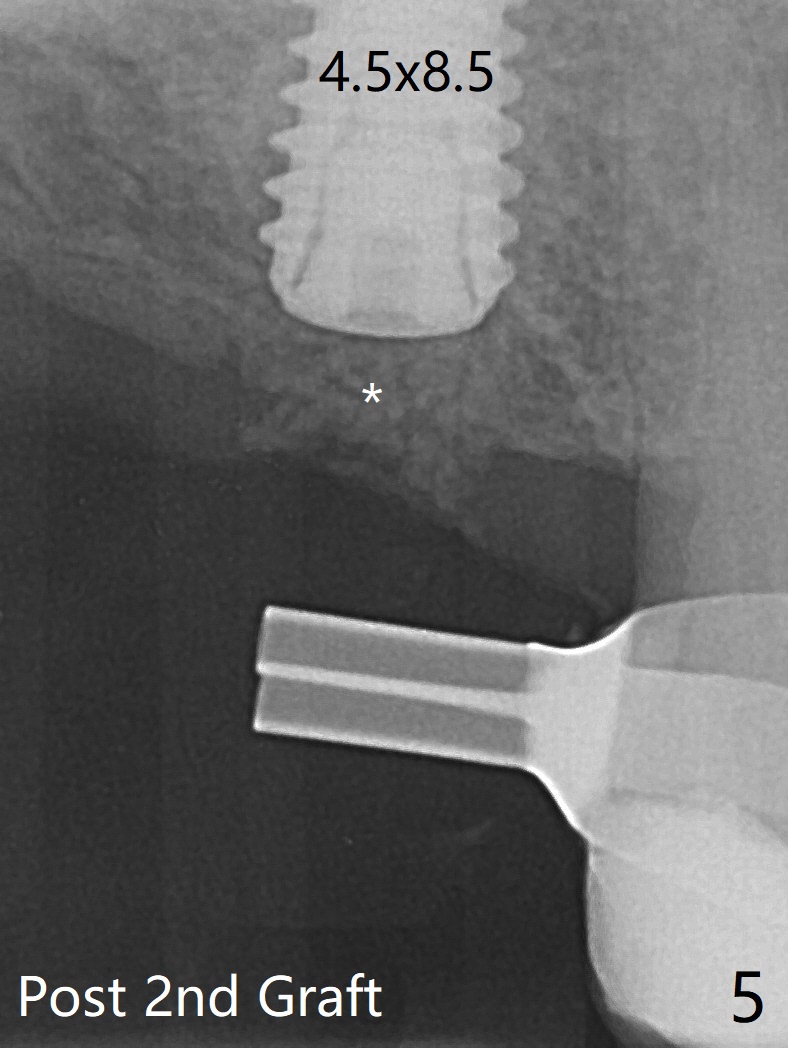

在导板协助下,顺利完成右上6钻洞,用圆钻穿过上颌窦底板,然后使用粘性骨粉(之前半张PRF膜)和4乘10毫米报废植体做第一次(图一,二),第二次(图三),第三次(图四,五)提升,退出报废植体后,拧入正式植体(4.5乘8.5毫米)。由于扭力大约10Ncm,放置愈合螺帽。植体颊侧骨壁比较低,螺帽上放置骨粉(图四,五:*),后者太多,再没有空间放置PRF膜,只好放置在骨粉表面,容易滑动,所以需要安置间隙保持器(图四,五)。在拍摄根尖片时,PRF膜丢失,只好在骨粉表面放置Teflon,然后放置牙周敷料,借助保持器固定。术后两周牙周敷料脱落,而间隙保持器仍在,下面牙龈基本愈合(图六,7)。今后使用导板做上颌窦提升,种植,最好使用导板的环形刀在牙龈上轻轻做过标记,然后用Biopsy Punch完整切除牙龈,放置于PRF上清液备用。如果植体扭力低,放置骨粉后,覆盖切除的牙龈,牙周胶水固定。